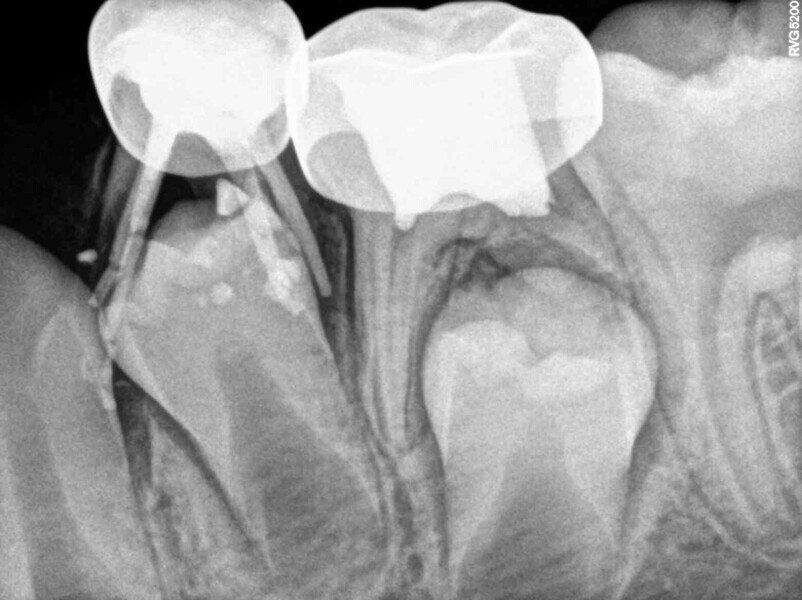

Cas 4 (Figs. 14 à 18)

Ce patient âgé de 4 ans et 6 mois présentait une douleur constante qui était apparue spontanément au niveau de la première molaire temporaire inférieure gauche, et persistait depuis plusieurs jours. Toutefois, aucun œdème facial ou gonflement du versant vestibulaire de la gencive n’était visible. Des caries profondes étaient présentes, mais il n’y avait ni mobilité dentaire ni profondeur de poche importante au sondage. La radiographie montrait un risque d’effraction de la cavité pulpaire lié à la lésion carieuse, et une atteinte de la zone de furcation correspondant à un défaut osseux. Une pulpectomie était le traitement de choix. L’élimination de la lésion carieuse a entraîné une exposition de la pulpe, mais aucun saignement n’a été observé. Une nécrose pulpaire a été diagnostiquée. Quatre canaux, deux mésiaux et deux distaux, ont été localisés et la dent a été obturée. Lors du second rendez-vous, la dent était asymptomatique et elle a été restaurée au moyen d’une couronne en acier inoxydable. À la visite de suivi à 30 mois, la dent ne présentait aucun symptôme et la radiographie a montré un processus éruptif normal.